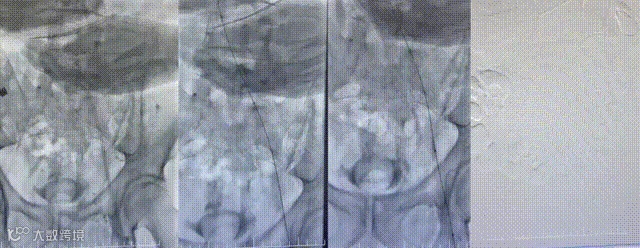

患者全程取俯卧位,左下肢常规消毒铺单,B超引导下穿刺左腘静脉,导入10F短鞘,经血管鞘造影,证实左腘股髂静脉血栓形成。鳅导丝配合单弯导管通过闭塞股静脉,造影证实导管位于下腔静脉。

导入10F天航外周血栓抽吸导管+天戟分离器于大腔导管行机械血栓清除

导入(10*60mm)球囊行髂静脉扩张

导入支架(14*100mm,)覆盖髂静脉狭窄处,再次造影见狭窄消失,股静脉回流通畅,原滤器内未见明显血栓形成,无造影剂外溢。拔管,穿刺点压迫止血,加压包扎。麻醉满意,术后患者安返病房。